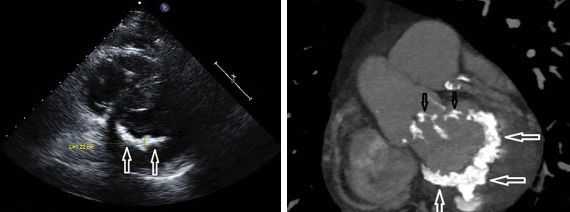

Другой важный инструментальный метод диагностики — эхокардиография (Эхо-КГ) . Эхо-КГ — это безболезненное ультразвуковое исследование, которое позволяет исследовать работу сердца в реальном времени. Эхокардиография покажет уменьшение эластичности клапана, его повреждение, размер отверстия митрального клапана и расстояние между его створками. Также при исследовании можно увидеть разрыв папиллярной мышцы и провисание клапанных створок в полость левого предсердия [4] [8] [9] .

По рентгенограмме при сочетанных пороках сердца нередко визуализируется гипертрофия миокарда, расширение камер сердца, застойные явления в легких и т. д. Наиболее информативным видом диагностики сочетанных пороков сердца служит эхокардиография с допплеркардиографией, дающая четкое представление о состоянии клапанного аппарата, наличии дефектов перегородок, патологической внутрисердечной гемодинамики.

С помощью эхокардиографии подтверждается диагноз митрального порока сердца и определяются превалирующие изменения (стеноз или недостаточность). Допплерэхокардиография помогает оценить величину регургитации и диастолического градиента давления на митральном клапане. При необходимости для получения этих сведений прибегают к зондированию полостей сердца и вентрикулографии.